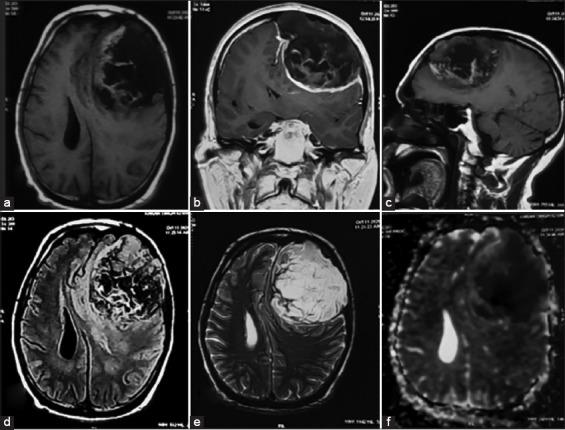

Intradiploic epidermoid tumors are uncommon and giant epidermoid with dural involvement is scarcer. We report a unique case of a giant frontal epidermoid tumor presenting without typical features of swelling or bulge in scalp. A 61-year-old male presented with the complaints of forgetfulness and headache. Contrast magnetic resonance imaging brain revealed a large left frontal epidermoid tumor. A tumor measuring 13 × 11 × 4 cm, involving the dura but sparing the brain parenchyma, was excised through left frontal craniotomy. Such a presentation of giant epidermoid tumor with dural involvement is highly unusual. Complete surgical excision is the final aim and vigilant follow-up for recurrence is a must.

板障内表皮样瘤并不常见,累及硬脑膜的巨大表皮样瘤则更为罕见。我们报告一例独特的巨大额部表皮样瘤病例,该病例无头皮肿胀或隆起的典型特征。一名61岁男性因健忘和头痛就诊。脑部增强磁共振成像显示左额叶有一个巨大的表皮样瘤。通过左额开颅手术切除了一个大小为13×11×4 cm、累及硬脑膜但未累及脑实质的肿瘤。这种累及硬脑膜的巨大表皮样瘤表现非常罕见。完整的手术切除是最终目标,必须对复发进行密切随访。